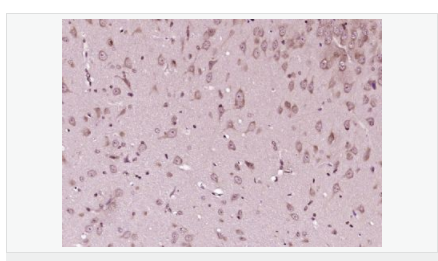

image.png

產品應用WB=1:500-2000 ELISA=1:5000-10000 IHC-P=1:100-500 IHC-F=1:100-500 Flow-Cyt=1μg/Test ICC=1:100-500 IF=1:100-500 (石蠟切片需做抗原修復)

交叉反應:Human,Mouse,Rat(predicted:Dog,Pig,Cow,Horse,Rabbit,Sheep,GuineaPig) 推薦應用:WB,IHC-P,IHC-F,IF,Flow-Cyt,ELISA